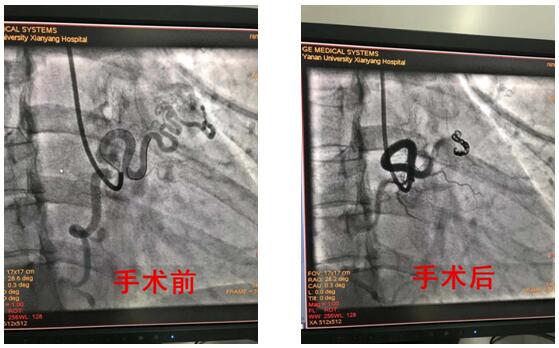

患者为39岁青年女性,反复发生心绞痛,冠脉造影示:右冠-左心房瘘道血管粗大,与右冠脉直径相当。结合患者症状,考虑右冠严重窃血引发胸痛症状。心内VIP介入团队在仔细询问病史、认真查体及详细的术前评估后于8月15日在导管室行弹簧圈封堵术,手术历经2小时,术程顺利,术后患者未诉不适,安返病房,术后严密监测血压、心率等生命体征均平稳。

冠状动脉瘘指冠状动脉与心脏或大血管存在先天性异常交通,多为先天畸形,以右冠状动脉瘘多见,占50%-60%,引入右心系统最为常见,占90%左右,以右冠状动脉--右室瘘常见,而通入左房左室相对罕见,心内VIP病区完成的这例手术恰恰是右冠状动脉--左房瘘。